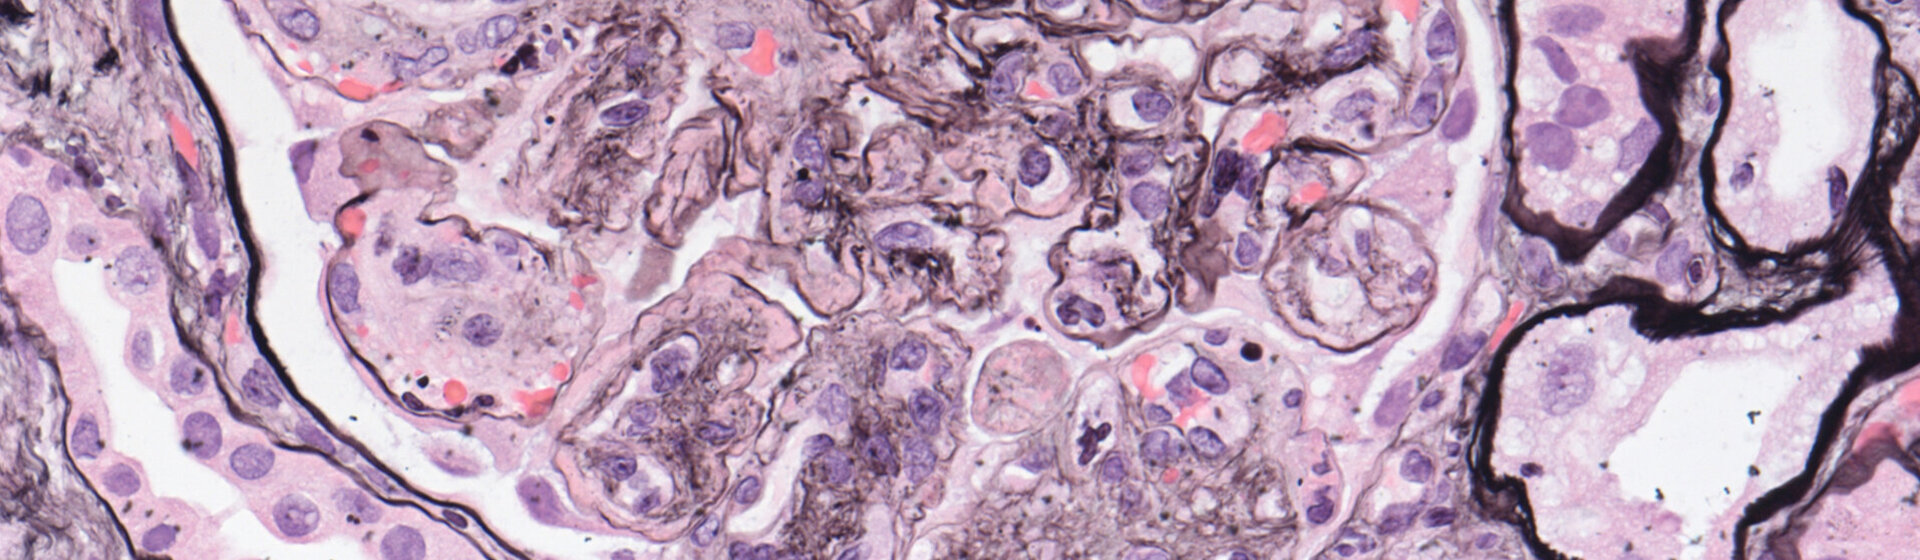

Die Nephrologie beschäftigt sich mit akuten und chronischen Nierenerkrankungen, der arteriellen Hypertonie (Bluthochdruck) und Störungen des Säure-Base- und Elektrolythaushaltes.